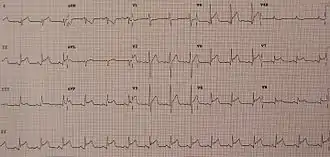

Myocardial inflammation may also be suspected based on ECG findings, but these findings are not specific to myocarditis.[38] The ECG finding most commonly seen in myocarditis is sinus tachycardia with non-specific ST or T wave changes.[38] But other findings that may be seen in perimyocarditis (a combination of pericarditis and myocarditis) include PR segment depression, PR segment depression with associated ST segment elevation, diffuse ST segment elevation (in a pericarditis pattern).[38] ST segment elevation was seen in 62% of people with myocarditis.[29] The presence of Q waves, a widened QRS complex, prolongation of the QT interval, high degree AV nodal blockade, and ventricular tachyarrhythmias are associated with a poor prognosis when seen on ECG in people with myocarditis.[38]

An electrocardiogram is one of the most common screening tools used in cases of suspected cardiac pathology, such as myocarditis. The findings that correlate with poorer outcomes are non-specific and include widened QRS complexes and QT intervals, partial or complete atrial-ventricular heart block, and malignant ventricular arrhythmias like sustained ventricular tachycardia or ventricular fibrillation.[48] Electrocardiogram findings of ST elevations with upward concavity and an early repolarization pattern, however, were associated with a better cardiovascular prognosis in general.[48]